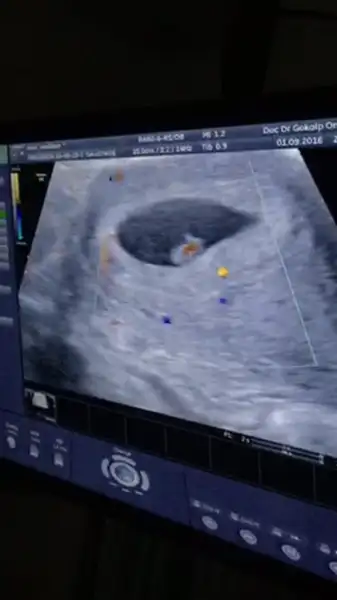

Burda da kız gibi :)) kesenin içinde sağ tarafa daha yakın.. bu da karından usg değilmiBu da tam 7+1 teyzesi

evet karından usg valla bizimki sürpriz olacak :) kıza da benzeten var erkeğe de :) ortalarda bir yerde sanki. allah hayırlısını versin hepimize :)Burda da kız gibi :)) kesenin içinde sağ tarafa daha yakın.. bu da karından usg değilmi

Evet canım karından usg :))Karından usg ise erkek gibi canım senin bebiş :)